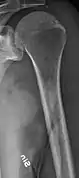

The diagnostic examination of a person with suspected multiple myeloma typically includes a skeletal survey. This is a series of X-rays of the skull, axial skeleton, and proximal long bones. Myeloma activity sometimes appears as "lytic lesions" (with local disappearance of normal bone due to resorption). And on the skull X-ray as "punched-out lesions" (raindrop skull). Lesions may also be sclerotic, which is seen as radiodense.[59] Overall, the radiodensity of myeloma is between −30 and 120 Hounsfield units (HU).[60] Magnetic resonance imaging is more sensitive than simple X-rays in the detection of lytic lesions, and may supersede a skeletal survey, especially when vertebral disease is suspected. Occasionally, a CT scan is performed to measure the size of soft-tissue plasmacytomas. Bone scans are typically not of any additional value in the workup of people with myeloma (no new bone formation; lytic lesions not well visualized on bone scan).

Multiple myeloma in the upper arm